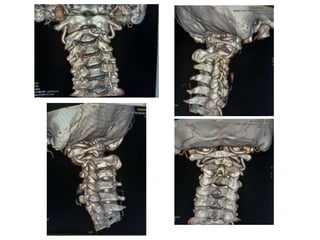

M Ramanamma is a 48-year-old female who presented with neck pain and paresthesias in her limbs for the past 5 months. On examination, she had decreased strength in her right upper and lower limbs and hypertonia in her lower limbs. Imaging showed atlantoaxial dislocation with compression of the cervical spinal cord at C1-C2, explaining her symptoms.